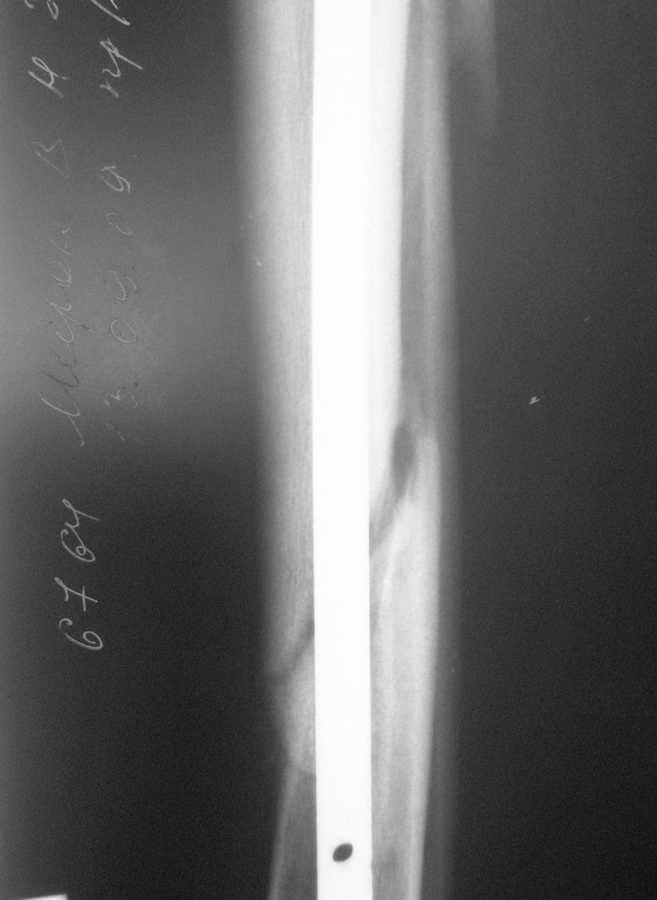

В январе 2009 года нами оперирована пациентка с переломом н\3 голени штифтом Expert. Динамизация через 4 месяца, пациентка при этом уже ходила с тростью. Дома периодически передвигалась без дополнительной опоры. В настоящее время - через 9 месяцев с момента операции периодически в вечернее время беспокоят ноющие боли в места перелома (не постоянно). При беседе выяснено, что боли чаще беспокоят после того, как днем она походит по дому без трости. Пальпаторно по гребню берцовой кости болей нет, но по задне-внутренней поверхности б\б кости пальпирутеся западение на уровне места перелома.В чем ошибка??? и что делать???

Недостаточная стабильность. Не использованы все возможности дистального запирания, нет самого проксимального из дистальных винтов. Два винта из трех коротковаты. В результате при диинамизации появился диастаз.

Тут есть уже опасность перелома стержня по ближайшему к перелому отверстию. Так что правильнее сделать реостеосинтез с рассверливанием. При введении гвоздя в дистальный отломок использовать отклоняющую спицу

или винт, чтобы стержень оказался не у переднего кортекса, как сейчас, а где и надо - посередине. Это обеспечит еще и встречно-боковую компрессию.

Значит, изначально в периферическом отломке гвоздь шел не по центру, а ближе к передней стенке. Это не очень хорошо.